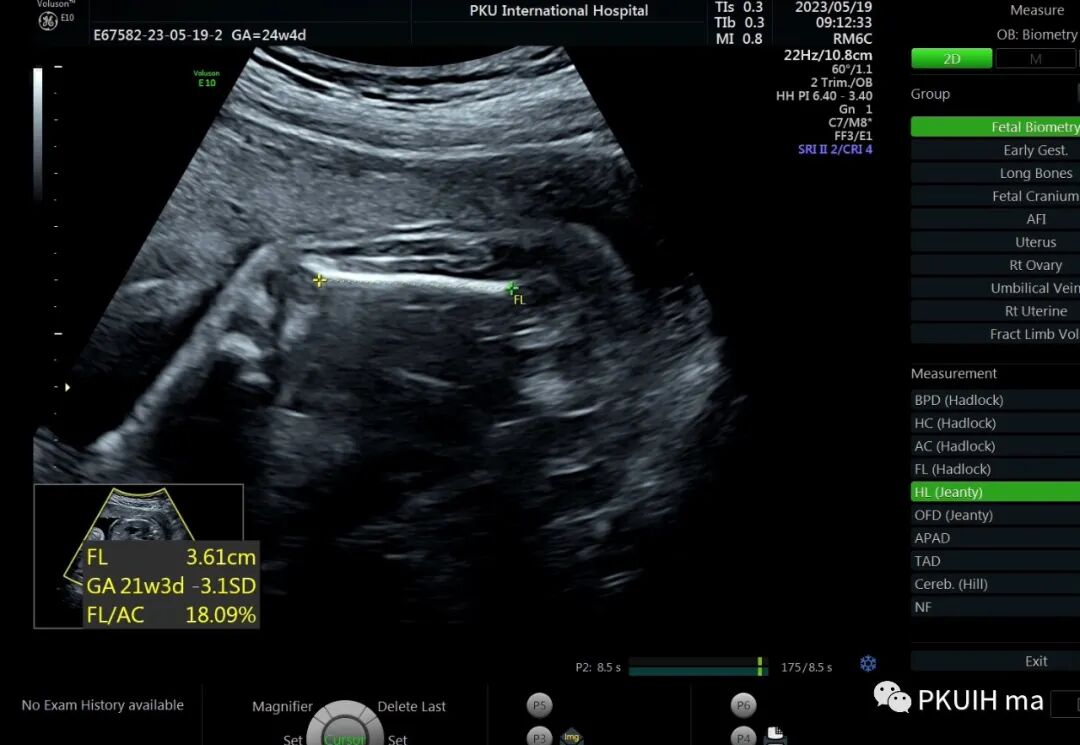

孕23周常规筛畸发现四肢长骨偏短,孕妇月经正常,核对早孕超声,孕周也没问题。

双顶径及头围正常,骨骼回声强度没有发现异常。

24周+复查发现还是肢体短,生长变慢